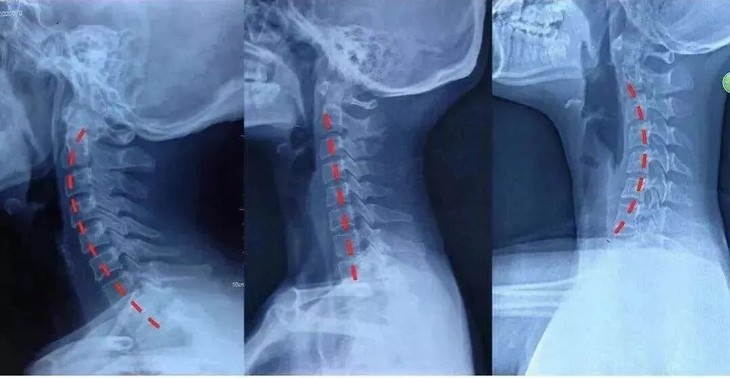

颈椎病对我们最直观的影响

就是会改变人体的体态

驼背、高低肩、富贵包以及颈纹

等等多种问题同时出现